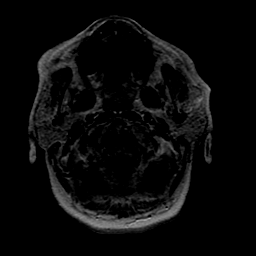

Stroke: proton density-weighted MR #1 -- Slice #0